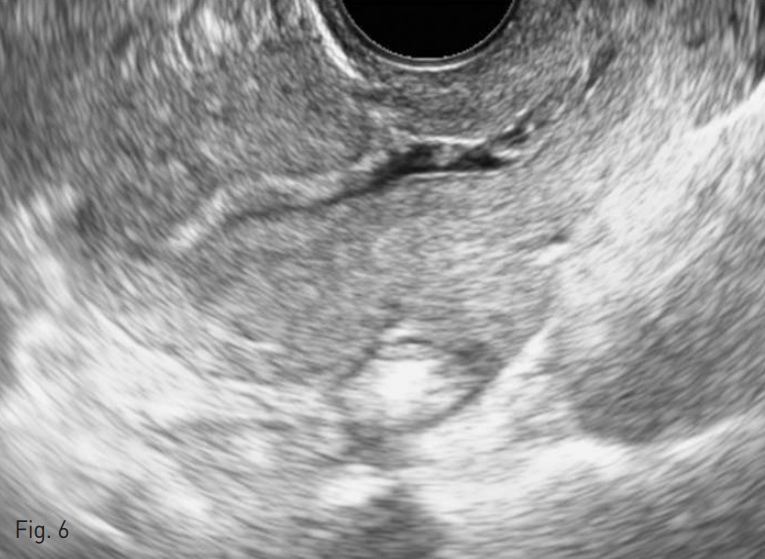

두 번째 색전술 직후 시행한 초음파 상에서 자궁 종괴는 여전히 관찰되었으나 색도플러를 적용하였을 때 종괴 내부의 혈관성은 거의 탐지되지 않았다. 이후 추적 관찰에서는 자궁 종괴의 크기도 점차적으로 감소하였고, 색전술 3개월 후 시행한 질식 초음파에서는 더 이상 자궁 종괴가 관찰되지 않았다 (Fig. 6). 색전술 1개월 후부터 정상주기의 월경을 보이고 있으며 색전술 직후 약간의 복부통증을 호소하였으나 색전술로 인한 주요 합병증은 발생하지 않았다. 환자는 총 4회의 화학요법을 시행 받았고 β-hCG는 음성으로 전환되었다.

Fig. 6

At three-month follow up, transvaginal ultrasound shows complete resolution of the uterine arteriovenous malformation.